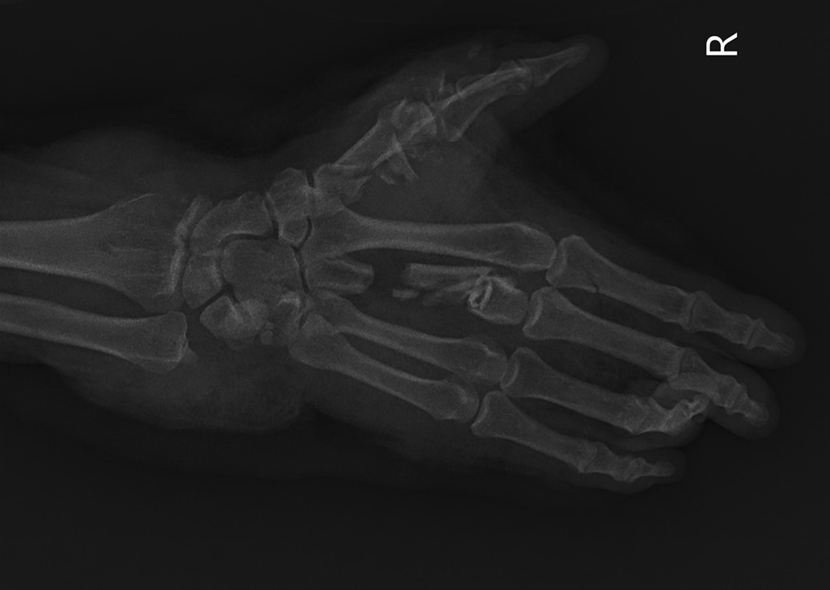

| Hình ảnh chụp X-quang cổ tay và bàn tay người bênh trước phẫu thuật. |

Tại bệnh viện, chị M. được tiếp nhận trong tình trạng tỉnh, da xanh, niêm mạc nhợt, đau, chảy máu, mất vận động cổ tay, bàn tay phải, vết thương phức tạp bàn tay phải và 1/3 dưới cẳng tay phải, lóc da rộng, lộ cơ, gân. Người bệnh được chỉ định phẫu thuật cấp cứu nối gân, kết hợp xương, nối phục hồi động mạch quay phải bị đứt.